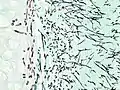

| Tomosynthesis of chronic fibrosing pulmonary aspergillosis | |

On microscopy, Aspergillus species are reliably demonstrated by silver stains, e.g., Gridley stain or Gomori methenamine-silver.[27] These give the fungal walls a gray-black colour. The hyphae of Aspergillus species range in diameter from 2.5 to 4.5 μm. They have septate hyphae,[28] but these are not always apparent, and in such cases they may be mistaken for Zygomycota.[27] Aspergillus hyphae tend to have dichotomous branching that is progressive and primarily at acute angles of around 45°.[27]